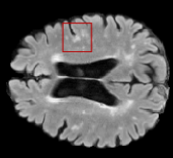

We evaluated our method in segmenting WMH from T1-w images using: a) Synthesized FLAIR images by treating the synthesis as a preprocessing step – we will refer to this method as offline synthesis; b) Synthesized FLAIR images using the proposed method, and c) without any synthesis – we will refer to this method as Unimodal. Baseline methods are illustrated in Figure 2

Table 2: Segmentation results for all proposed methods, each column represent a different slide in the image, blue areas are regions which were correctly labeled, false positives are shown in green, and false negatives in yellow

In order to better understand the above results, we visually analyzed the output segmentation performed for each method. Table 2 shows the results for three different slices (one slice per column). As illustrated, the proposed method is able to produce less false positives. It is also important to note that, unimodal segmentation is the one that produces more false positives, showing the advantage of using synthetic data. Regarding the nature of false positives, it can be easy to see in the third column a large number of false positives are on the border of periventricular lesions for the Unimodal method in comparison to the proposed method. Also from the first and second column, it can be observed that Unimodal tend to produce more small regions of false positives near to cortical areas. Removing such false positives requires additional post-processing steps, therefore, it is of value avoid this kind of over-segmentation. It can also be noted that synthesis methods tend to produce the same kind of false negatives, this may be due to the blurring effects in synthesized images since the information available during testing is limited – which otherwise is available from a FLAIR sequence.